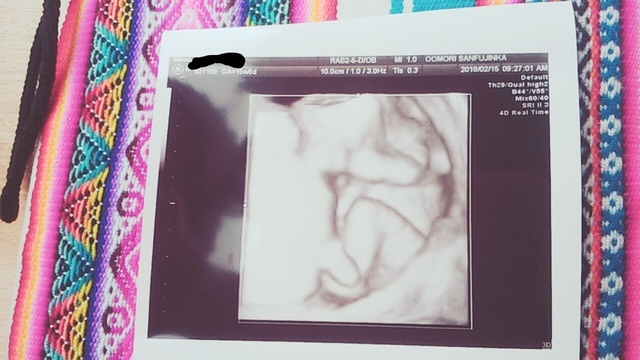

15週6日(15w6d・男の子)|ぷるぷる姫 さん(33歳)

エコー写真撮影時のエピソード:

顔が見えたとき。手で顔を触って、撫でているようで、すごく愛おしく感じました。今まで2Dの画像のみだったのが、3Dで顔の形、手の形が見え、お腹の中で育っていく様子を感じることが出来ました。

発育過程は教科書的には十分理解していますが、自分のお腹の中でその過程が進んでいるのはとても不思議な気持ちでした。